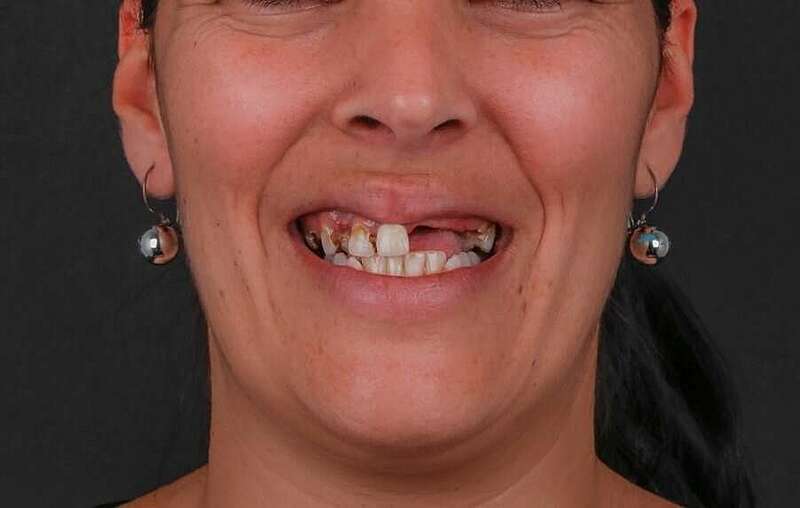

Avant